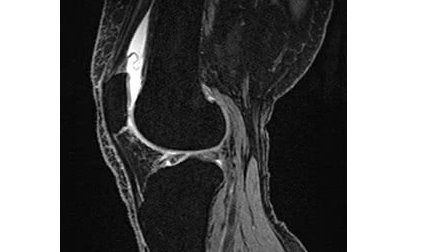

诊断为变形性膝关节病 等级4(末期)。

可见骨坏死及脆弱性骨折、半月板消失、可见多个骨刺